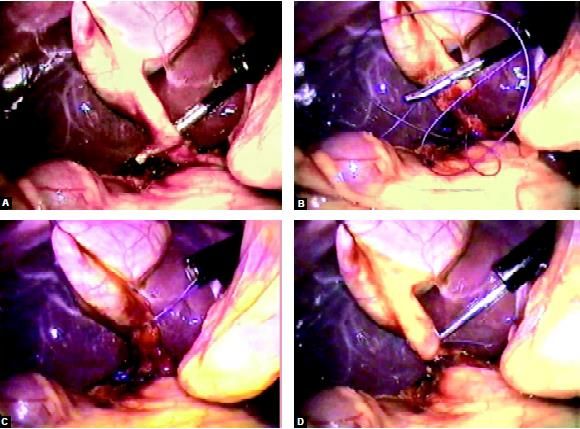

An extracorporeal knot can be applied for a cystic duct without any problem after a nice dissection of the cystic pedicle. The knot which is tied over the cystic pedicle is used to pull the neck of the gallbladder up and with the help of hook GB is separated from the liver. Patients undergoing cholecystectomy by the two-port method had a better resumption of diet and less postoperative pain. Two-port cholecystectomy is technically feasible and may further improve the surgical outcomes in terms of postoperative pain and better cosmetic value. The two-port cholecystectomy should be performed by an experienced laparoscopic surgeon because skilled choreographic hand movement is very important in this surgery. Bimanual skill and correct interpretation of anatomy is a must before proceeding for this technique. We do not recommend two-port cholecystectomy as a routine procedure.

Clip or extracorporeal Meltzer knot is applied over cystic artery and duct

The extracorporeal knot of the cystic duct is used to pull the neck up and to expose bed of the gallbladder